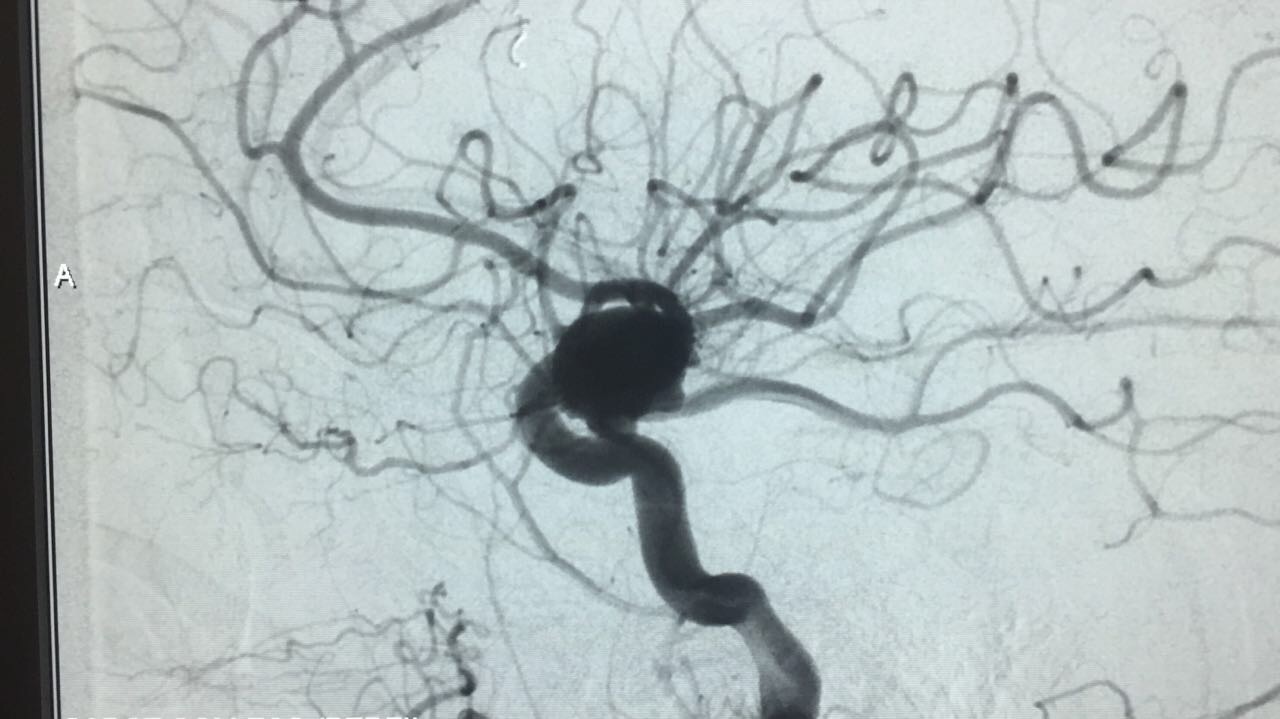

Embolização de Aneurisma segmento Oftálmico

Paciente foi então encaminhada ao setor de hemodinâmica sendo realizado Angiografia cerebral Digital e evidenciado aneurisma de segmento oftálmico da artéria carótida interna esquerda. Realizado embolização do aneurisma com microespirais, sem intercorrências. A paciente permanece em bom estado geral e neurológico recuperando em pós operatório imediato.